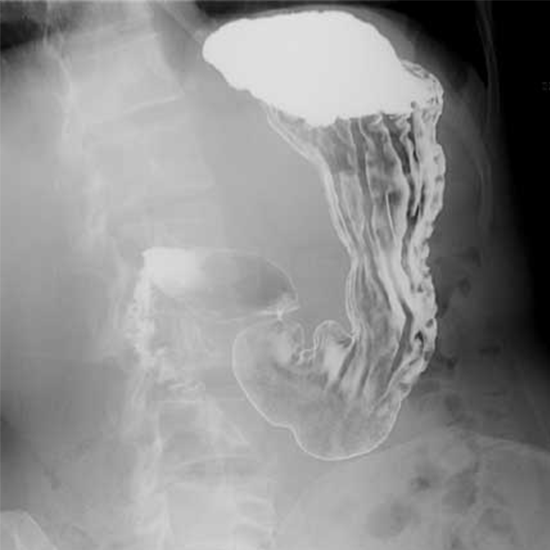

Upper Barium Gastrointestinal tests are used to examine the upper surface and contour of the gut. This test can detect tumors, polyps, and ulcers in the stomach, gullet, and upper gut region (duodenum).